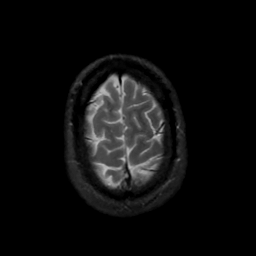

MR Study #16, June 23, 1991 -- Slice #44

[Home][Help][Clinical][Tour 1][Tour 2] Slice 44